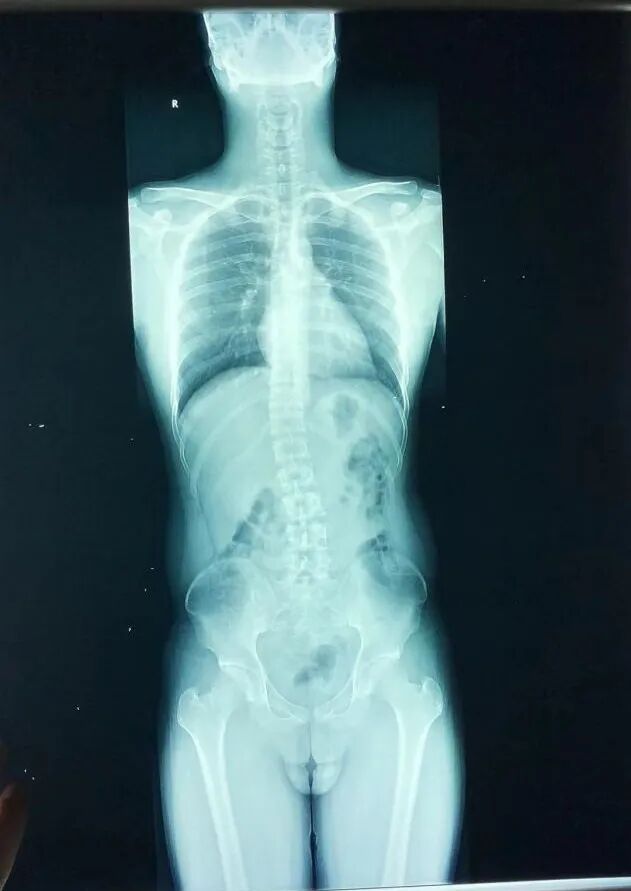

治療前側(cè)彎8度,治療后基本0度